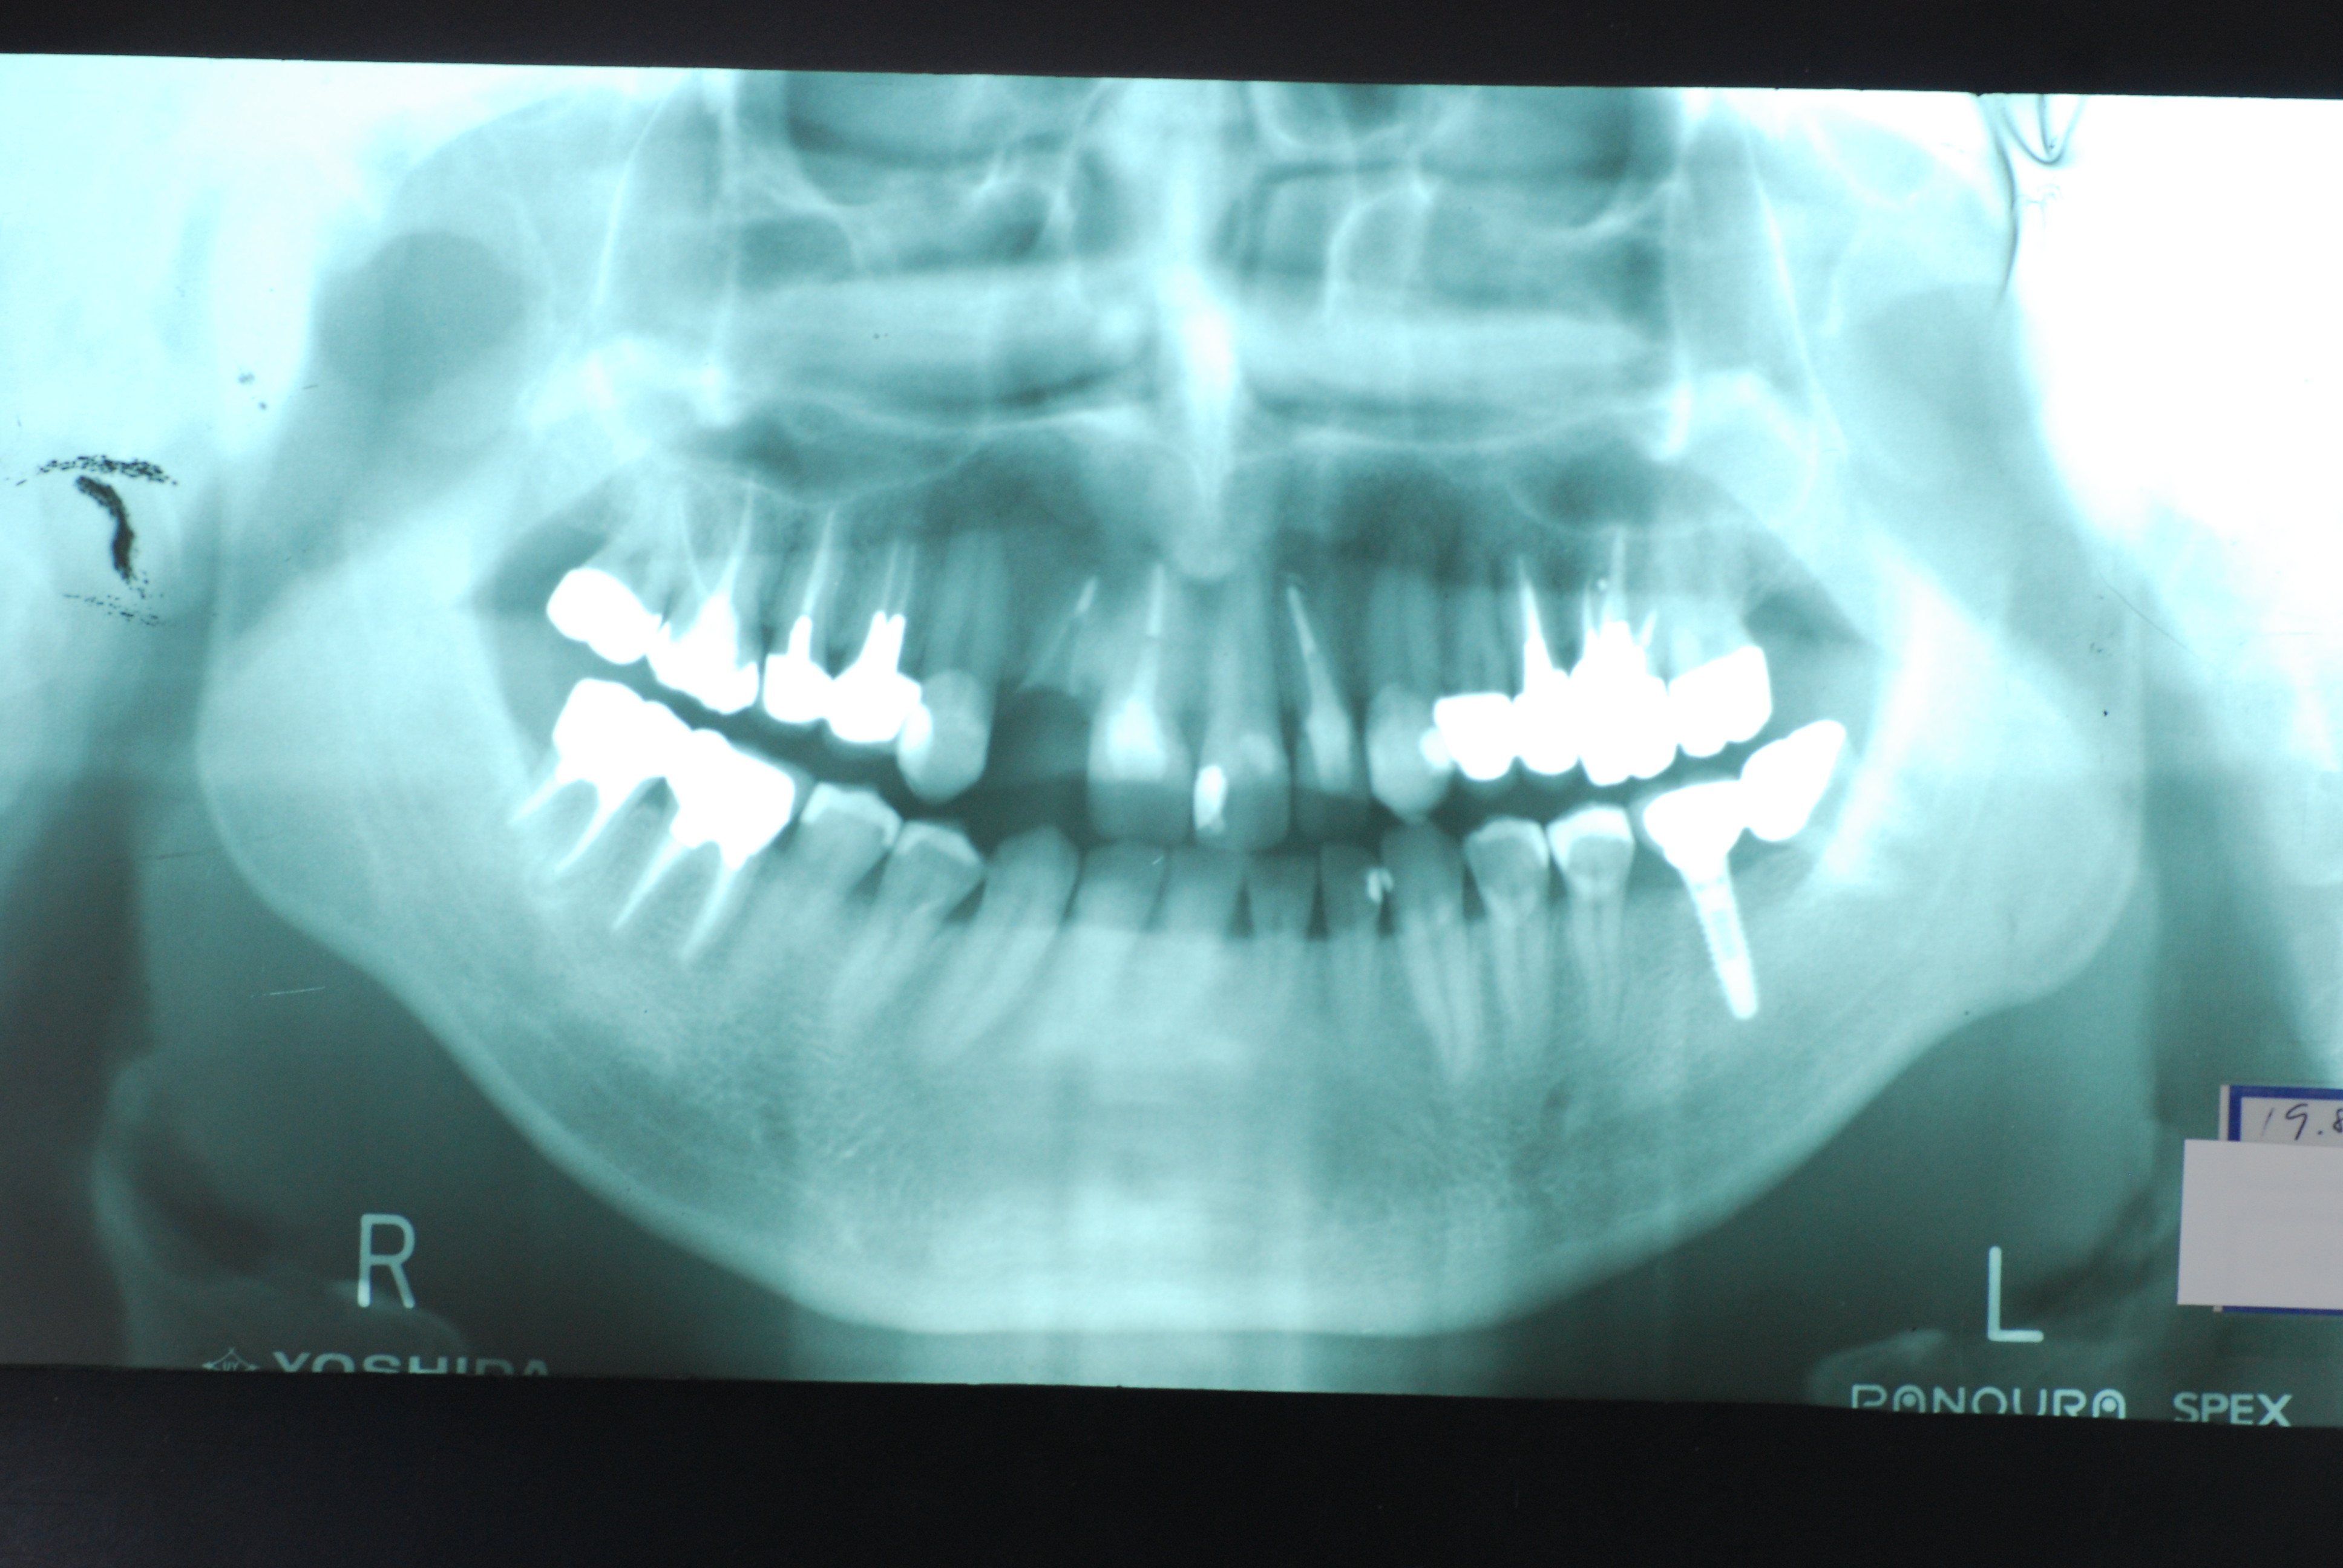

現実を見ればお口の中には“異物”である金歯、銀歯、セラミック、インプラントのオンパレードです。

必ずばい菌が侵入しないようにしてばい菌である虫歯を除去します。

銀歯の下はばい菌だらけです。こういうのはよくあります。取り残しですね。![treatment_05[1]](https://livedoor.blogimg.jp/netdental/imgs/3/a/3ad019d0-s.jpg)